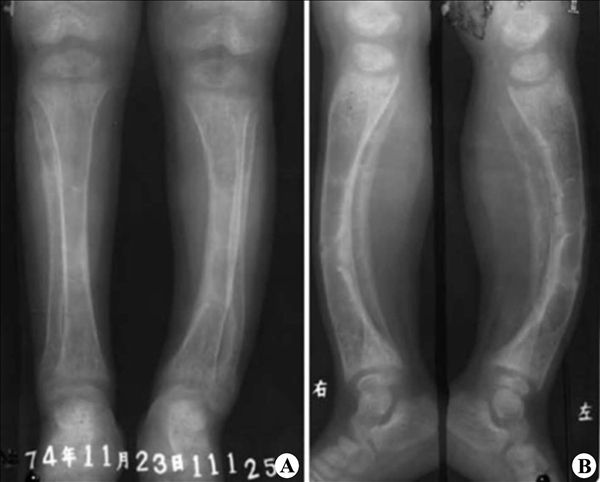

【影像表现】:X线正侧位片(A、B)示双下肢骨质密度减低,结构模糊,提示矿化不足。干骺端模糊、杯口状膨大,双下肢变形呈“O”形腿。